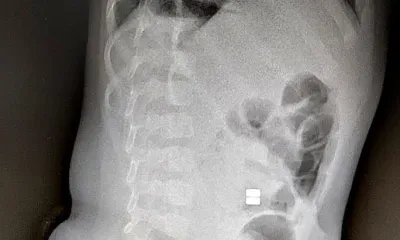

Фото ТЕЛЕПОРТ.РФ